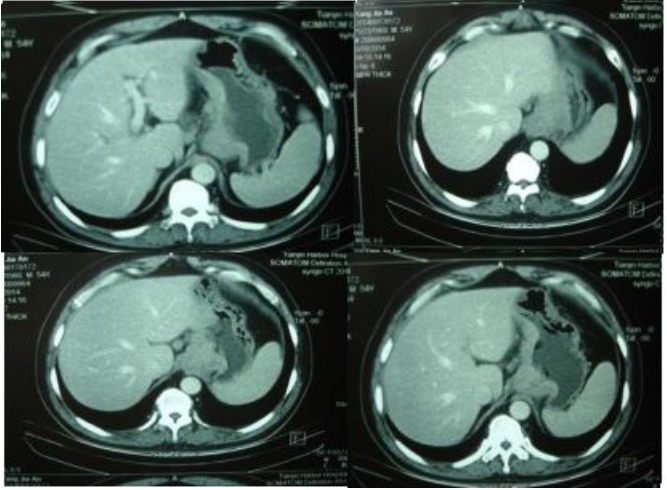

胃镜:进镜40cm见息肉样病变延及贲门及胃底、胃体,胃腔狭窄,尚能通过镜身,胃体中部近半周弥漫性粘膜破坏区,咬检病理(胃底)中分化腺癌,(贲门)粘膜急慢性炎症,腺体重度不典型增生,于炎性渗出及坏死组织中见异型细胞巢;HER2过表达,IHC 3+。肿标:CA199 742U/ml;CEA 78U/ml。胸腹盆CT:贲门胃底胃壁及胃体上部胃壁不规则增厚;下纵膈贲门周围肝胃韧带区及腹膜后多发肿大淋巴结;腹盆腔少量积液。

2014-9于当地行腹腔镜探查术,术中见:贲门胃底及胃小弯处可及7*5cm肿物,肿物与胃小弯成冰冻状,无法推动,且与胰腺表面广泛浸润,胃左动脉旁淋巴结融合成团, 术中判断肿瘤处于晚期,无法手术切除,放弃手术。术后病理及诊断(pT4bNxM1)。

▲胸腹盆增强CT(2014.09.02)

小结:中年男性,探查术后患者,晚期胃癌诊断明确,肝门区,腹膜后多发转移。讨论目的:制定进一步治疗方案。

影像科:从目前CT考虑,贲门部肿瘤累及胃底胃壁,伴腹腔多发转移,分期明确。